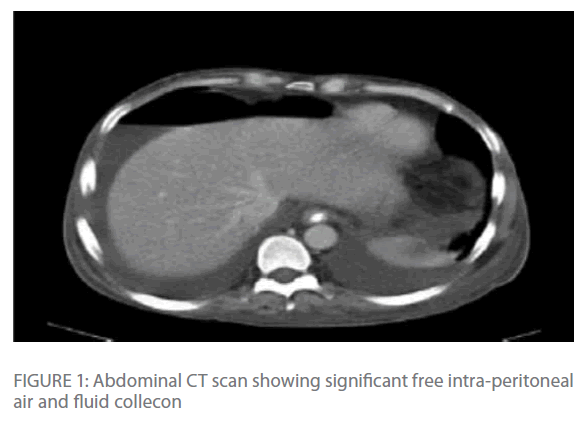

Repeated chest radiographs revealed gas under his diaphragm, which raised the suspicion of a perforated viscous. Subsequently, a CT-scan of his chest and abdomen revealed significant intra-peritoneal air and fluid collection with edema and transmural air in colonic wall (Figure 1 & Figure 2) with normal lung parenchyma.

Figure 1: Abdominal CT scan showing significant free intra-peritoneal air and fluid collecon